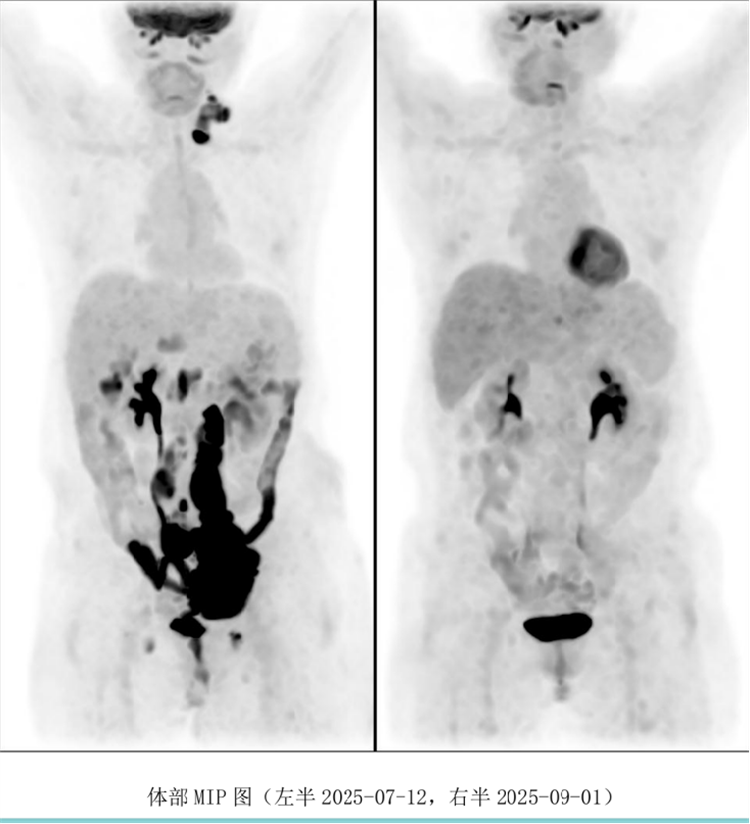

病例匯報(bào)環(huán)節(jié)由我院淋巴瘤科張薇醫(yī)生帶來(lái)了三例精彩紛呈的難治復(fù)發(fā)彌漫大B淋巴瘤CAR-T治療的病例。

病例過(guò)程跌宕起伏,從橋接治療到靶點(diǎn)的選擇,并發(fā)癥的處理都極具代表性。張醫(yī)生詳盡分享了患者在治療過(guò)程中的挑戰(zhàn)、決策依據(jù)以及CAR-T細(xì)胞治療后的驚人緩解與轉(zhuǎn)歸,充分展示了CAR-T技術(shù)為晚期患者帶來(lái)的突破性生存希望。